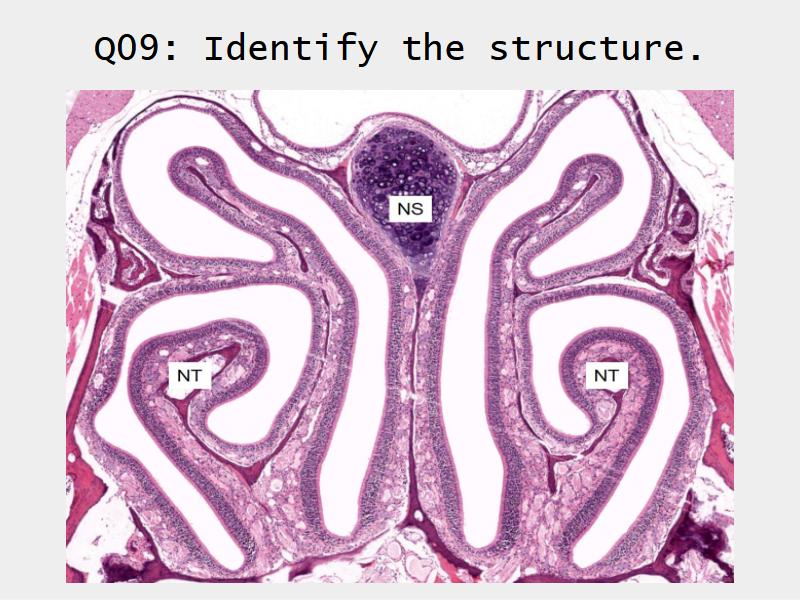

Slides: Respiratory System

- Slide 71: Nostril

- Slide 108: Olfactory epithelium

Olfactory epithelium

Function of the nasal cavity?

Function of the nasal cavity?

- Warm

- Moisture

- Filter

- Smell